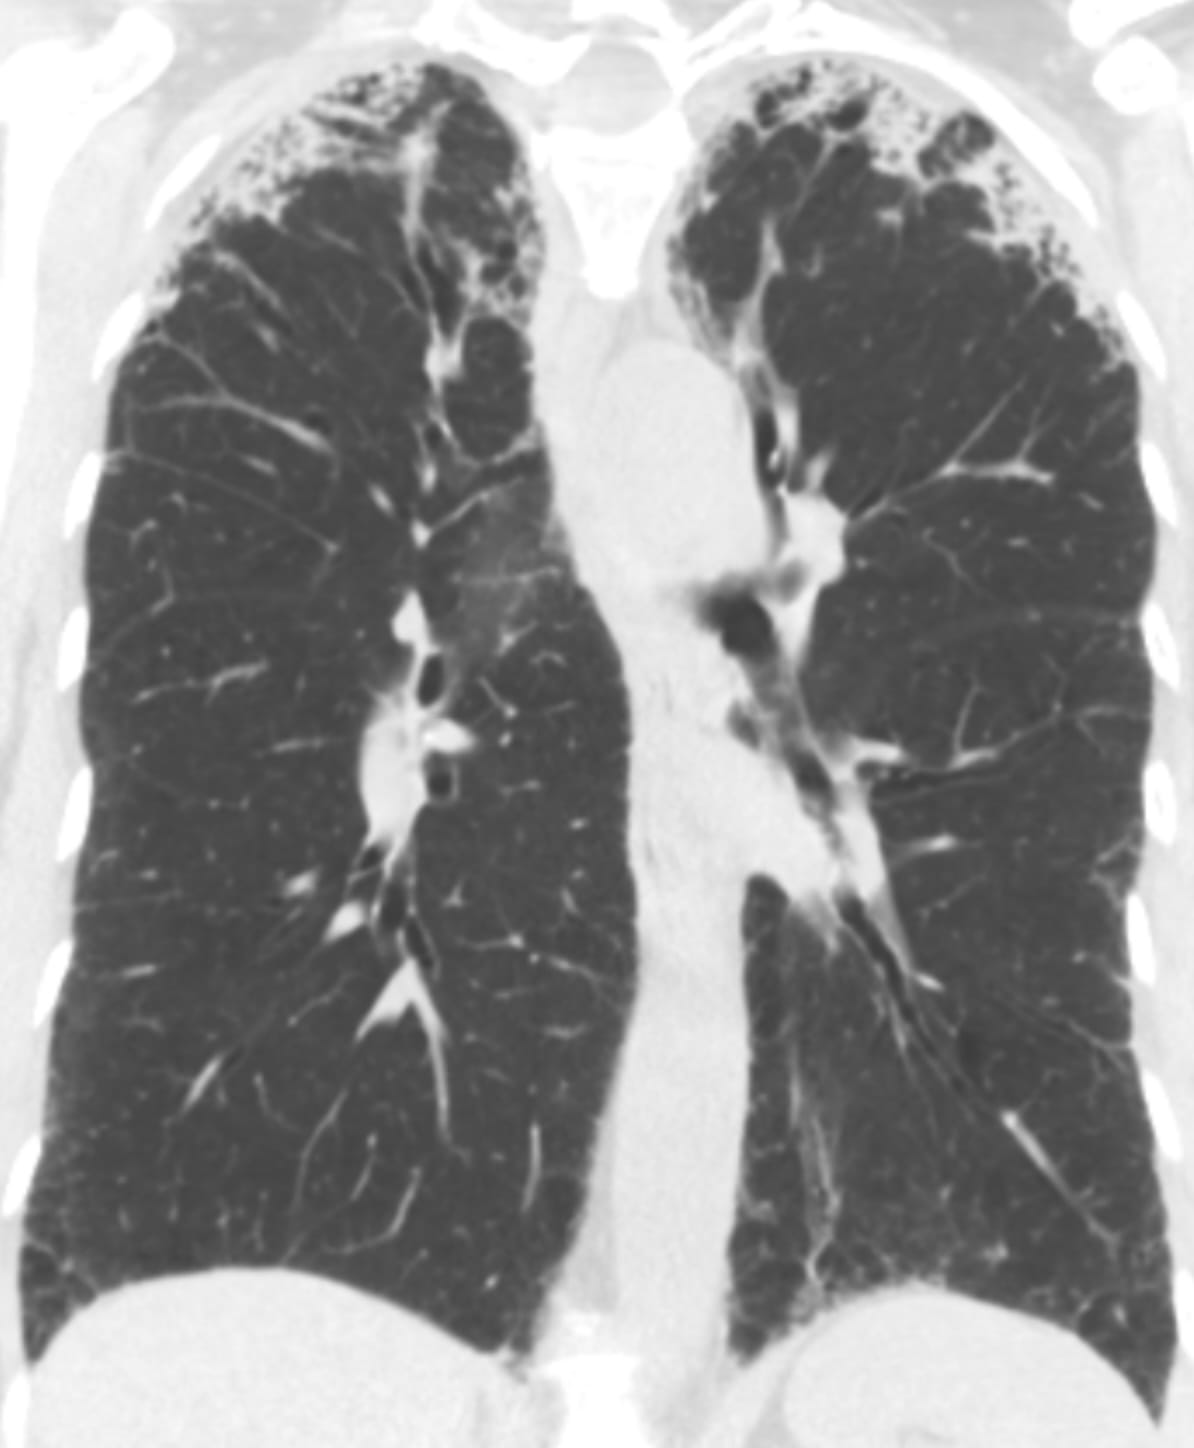

- Usual Interstitial Pneumonia